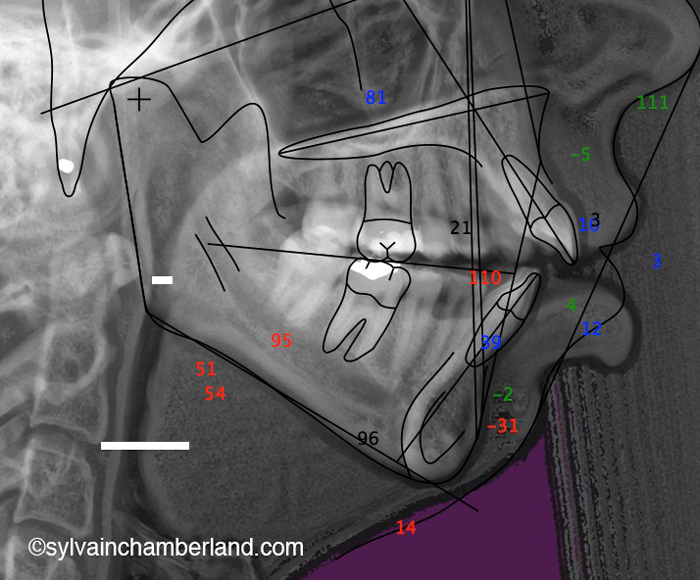

Dans ce cas-ci la béance s’explique par un excès vertical du maxillaire. Observez, sur la radiographie céphalométrique de gauche, la grande distance entre les racines des dents postérieures supérieures et le palais. C’est l’indication d’un excès vertical. La longueur de la branche montante est normale et l’angle goniaque est à la hauteur de la 2e vertèbre cervicale.

Vous pouvez aussi comparé avec le tracé céphalométrique du cas précédent avec résorption des condyles. Il est facile de constater que l’angle goniaque est au niveau de C2 et que l’espace oropharyngé est plus large.

Ces deux cas illustrent une malocclusion avec béance antérieure, mais deux étiologies totalement différentes. Dans le 1er cas, la béance antérieure s’explique par la résorption condylienne. Dans le 2e cas, la béance s’explique par un excès vertical du maxillaire supérieur.

Le 2e cas a subi une chirurgie orthognathique bimaxillaire conventionnelle avec repositionnement supérieur du maxillaire, ostéotomie mandibulaire et génioplastie.